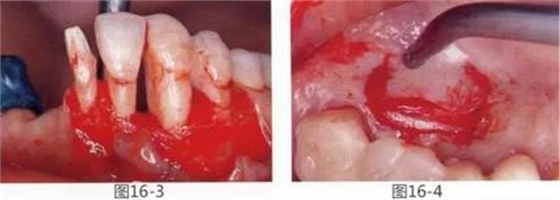

圖16-3 通過牙周外科將牙周袋去除,獲得附著齦,牙槽嵴增大。

圖16-4 從腭側(cè)采集結(jié)締組織瓣。